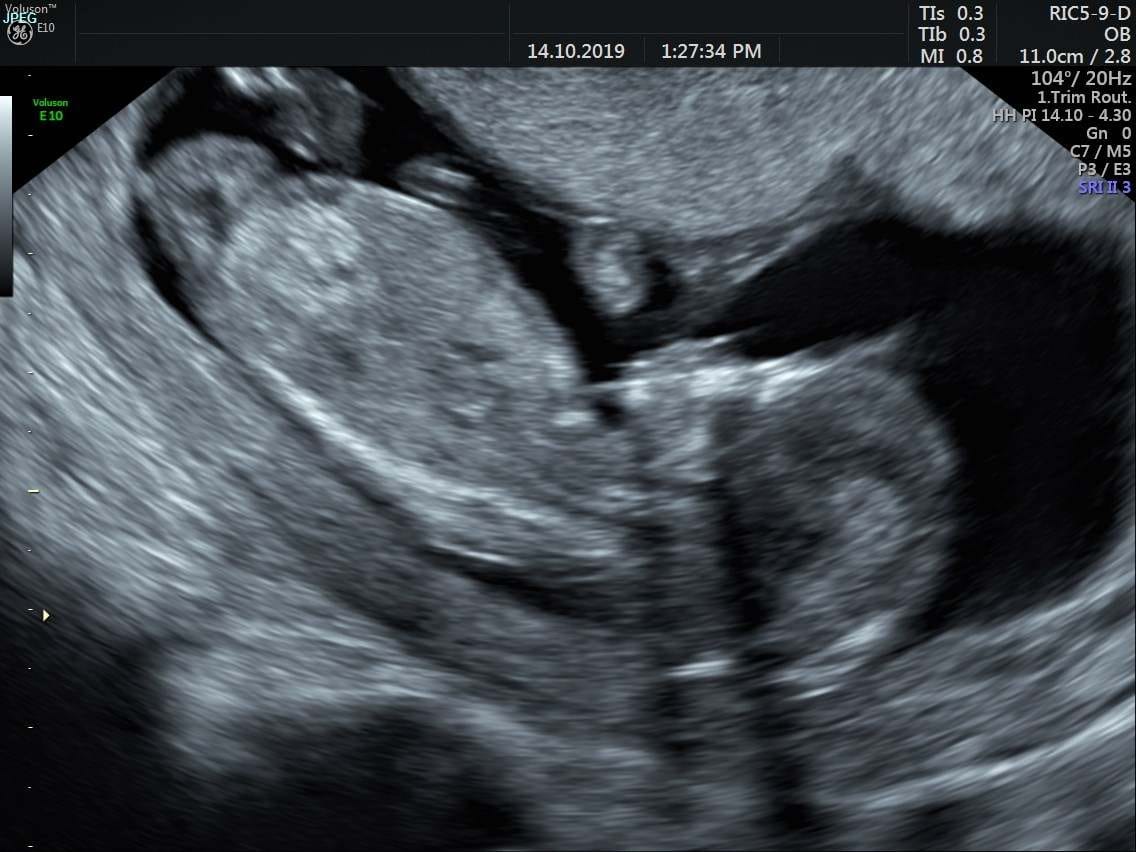

Ahojky holky 🙂 tak jsem po prvnim screeningu a dopadl dobre 🙂 vyloucily nam riziko na ruzne syndromy,pohlavi zatim nevime ale tak jsme ve 13tt to je jeste brzy 🙂 podle UZ mame termin 17.4. 🙂 koho screen teprve ceka preji vam hodne stesticka🍀 slyset srdicko ditete je to nejkrasnejsi co jsem kdy slysela,manzel byl se mnou a mel slzy v ocich je to vazne nepopsatelny pocit,kort kdyz jsme po jednom SP a tohle je pro nas vazne obrovsky dar 🙂 ❤